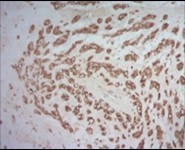

Figure 7.Parachordoma depicting immune reactivity to S100 protein 16.

Figure 8.Parachordoma demonstrating immune reactivity to vimentin 16.